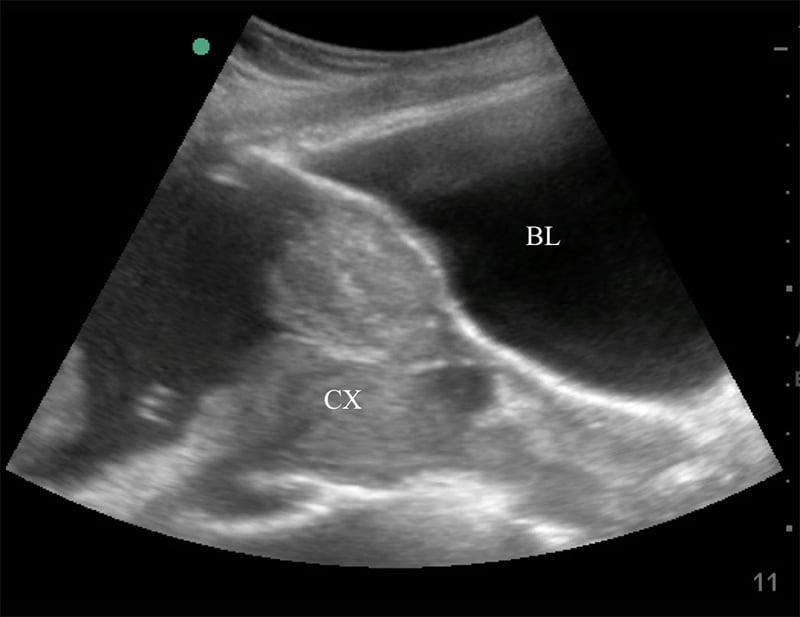

Figure 35. Sagittal transabdominal view of the pelvis revealing the anechoic urinary bladder (BL) and a normal cervix (CX) just below.

Figure 36. Sagittal transabdominal view of the pelvis similar to Figure (prior), with hyperechoic placenta (PL) covering the internal cervical os (CX).